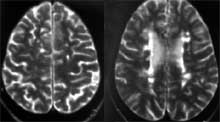

ВПРС у 195 (28,5%) хворих був наступним стадією РРС, відрізнявся характерною динамікою клінічних симптомів: поступовим наростанням рухових, координаторних порушень без чітких ремісій. На МР-томограмах головного мозку явно переважали осередки підвищення інтенсивності сигналу в Т- 2W режимі, вони поєднувалися з одиничними вогнищами зниження інтенсивності сигналу в Т-1W режимі. Виявлявся також великий атрофічний процес з розширенням шлуночкової системи мозку, субарахноїдальних просторів, особливо в проекції тім'яних, в меншій мірі скроневих, лобових часток (Рис. 2а, б).

Мал. 2а, б. Великий атрофічний процес з розширенням шлуночкової системи, субарахноїдальних просторів з вогнищами демієлінізації при ВПРС, (а, зліва) - півкулі, (б, справа) - стовбур головного мозку.